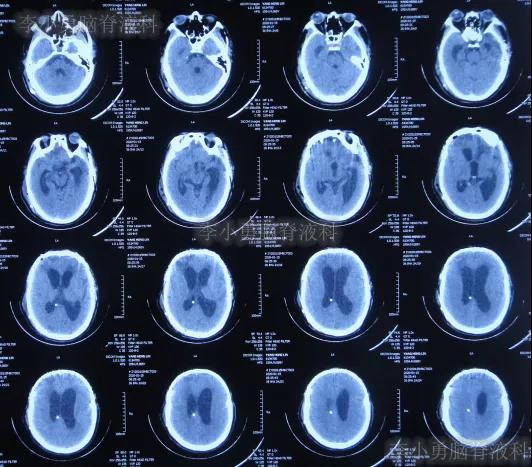

在第4家医院治疗26天,仍间断性发热、大小便失禁加重,住院期间曾2次查头颅CT(2020年2月27日(图-28)、2020年3月12日(图-29))示脑室仍扩张。

图-28:2020年2月27日头颅CT

图-29:2020年3月12日头颅CT

二、李小勇脑脊液科治疗过程和结果

2020年3月18日(颅脑外伤开颅术后149天即颅骨修补术后95天即第2次脑室腹腔分流术后62天,先后经4家医院治疗后仍意识模糊,大小便失禁,脑积水,间断发热近2月)转住入李小勇脑脊液科。入院时:意识模糊,大小便失禁,体重较前明显减轻,体温高38度左右;头部可见引流管走向;右侧肢体活动差些;鼻饲流食(图-30);入院时头颅CT示颅骨修补术后、脑室引流术后仍脑积水,有水肿(图-31)。

图-31:2020年3月18日头颅CT